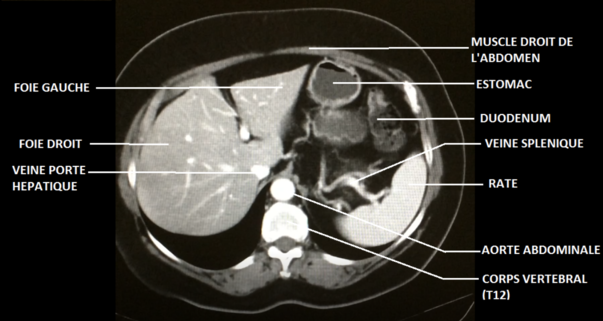

Sur ta coupe, le corps de la

vertèbre serait quant à lui plutôt carré, avec ses deux processus transverses latéraux et son unique processus épineux postérieur. Je t'ai joint ci-dessous le schéma de l'an dernier sur lequel figure le rachis

- coupe axiale abdomen.png (122.43 Kio) Consulté 4244 fois